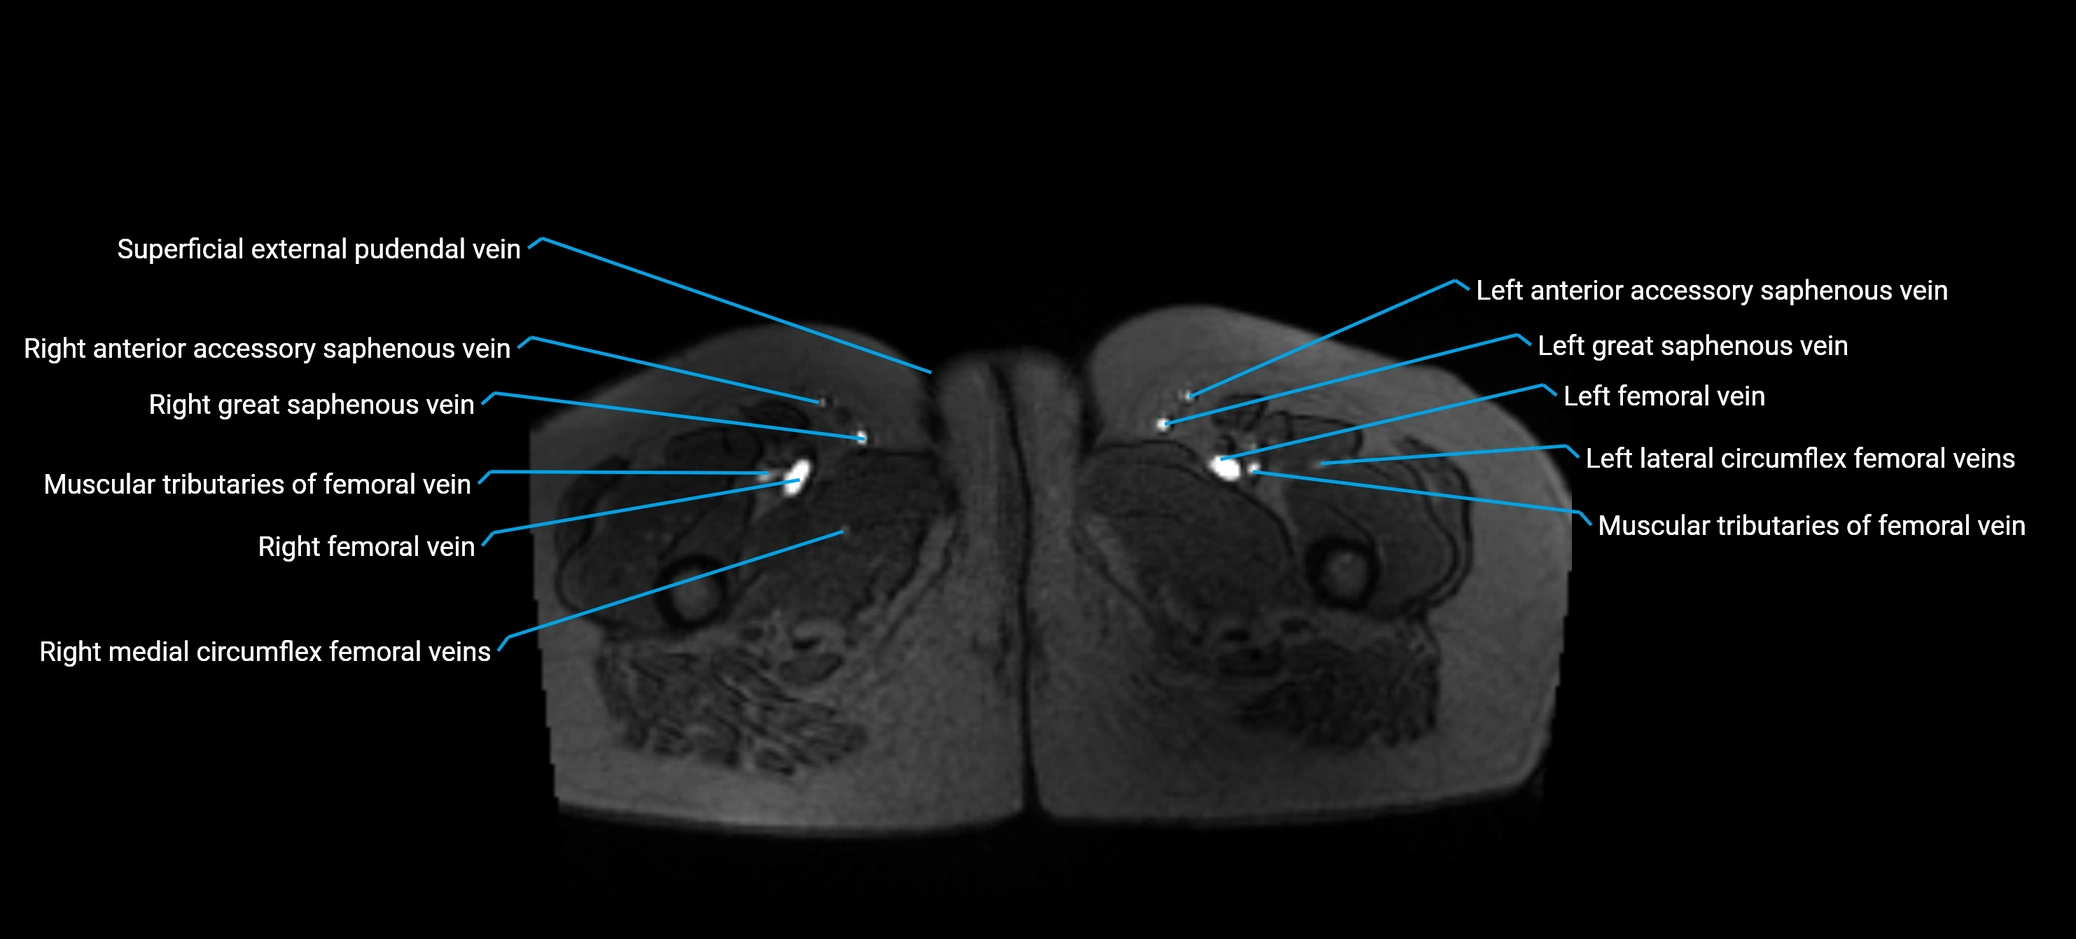

MRI image

image